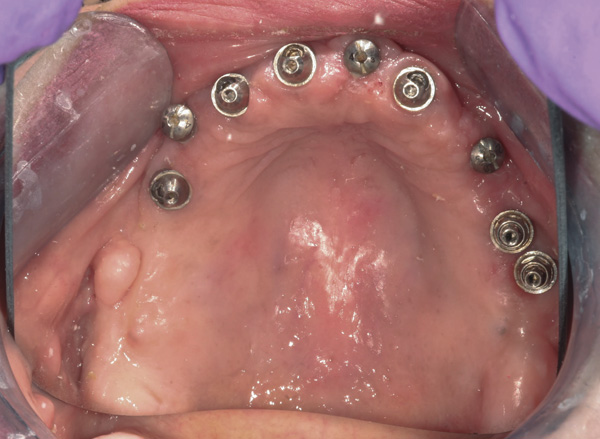

Background: The patient in this case presented with a failing dentition due to generalized severe periodontal disease with secondary endodontic lesions. She adamantly refused to wear removable transitional prostheses. Full maxillary and mandibular extractions were performed in the first phase of treatment. Not all implants could be placed in this initial phase due to the need for healing of certain grafted sites. The implants placed in this first phase were loaded with conical abutments and, in some cases, their angulated counterparts (Figure 16 and Figure 17). These stock titanium abutments were selected to avoid the need, as in Case 3, to change or remill the more costly custom abutments. They also have the advantage of making it unnecessary to use temporary cement near and around surgical sites, as they use occlusal screws only for retention.

Figure 16 First-phase implants loaded with conical abutments and, in some cases, their angulated counterparts.

Figure 16

Figure 17 First-phase implants loaded with conical abutments and, in some cases, their angulated counterparts.

Figure 17